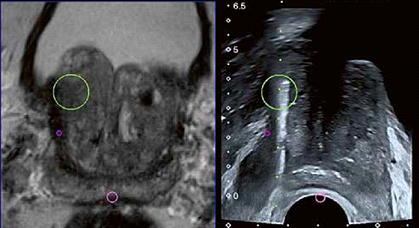

Hoje em dia a biópsia padrão é realizada com auxílio do ultra-som, utilizando-se fusão de imagens da ressonância magnética com a imagem do ultra-som. Desta maneira se consegue amostrar exatamente a área suspeita que aparece na ressonância realizada antes da biópsia. O sensor do ultra-som é colocado no reto, a próstata visualizada e as imagens sincronizadas com as imagens da ressonância previamente carregadas no aparelho.

Hoje é realizado o ultra-som trans-retal mas se faz acesso da agulha de biópsia elo períneo. (Imagem) Este via permite acesso a regiões abaixo e acima da uretra, muito difícil na biópsia transretal, além de diminuir muito a possibilidade de uma infecção.

Inicialmente é feita amostragem da área suspeita e em seguida um “mapeamento” ou amostragem randomizada da próstata utilizando-se imagens e posicionamento permitidos pelo ultra-som.

Em cada estudo são retirados 12 fragmentos de amostragem e de 2 a 4 das áreas suspeitas na ressonância.

Imagens simultâneas da lesão alvo na REMA (E) e a imagem do ultra-som (D) com a agulha no local suspeito para retirada do material a ser examinado.